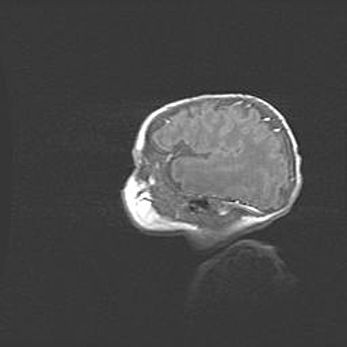

Неполная лизэнцефалия (пахигирия). Открытая гидроцефалия.

Возраст: 17 дней

Вес: 3110 г

Пол: мужской

Окружность головы: 33,5 см

Срок гестации: 35-36 недель

Лизэнцефалия—недоразвитие корковой пластинки и мозговых извилин в результате нарушения миграции нейронов коры. Поверхность мозговых полушарий гладкая. Микроскопически выявляется отсутствие нормальных слоев коры и скопление групп нейронов в подкорковом белом веществе.

Пахигирия—уменьшение числа вторичных извилин. В пораженном полушарии нервные клетки образуют толстый недифференцированный слой с неправильно расположенными нервными волокнами и группами гетеротопных клеток. Нервные клетки незрелые. Белое вещество истончено. При этом нередко аномально развит корково-спинномозговой путь.